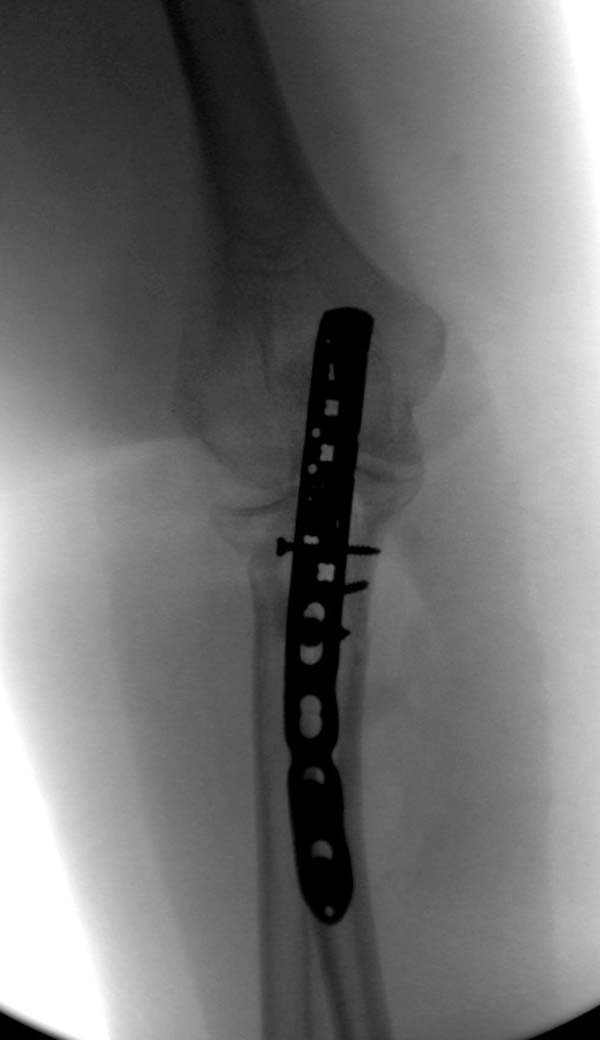

Здесь представлены несколько случаев и как видно больше больных с серьезными повреждениями, чем изолированные..

В первом случае перелом Монтеджи, где доперационно сделано оценка положения головки к остальным элементам под рентгеном. Учитывая правильность взаимотношении произведена фиксация только локтевого отростка, Второй случай, заменена на протез, и третий, кроме фиксации головки - реконструкция capitellum латерального мыщелка.